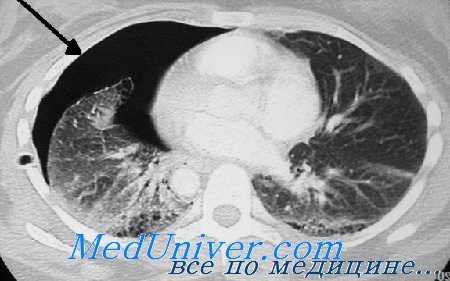

Важно выполнить рентгенографию грудной клетки сразу же после установки трубки. Это поможет подтвердить ее правильное расположение и оценить полноценность эвакуации жидкости и воздуха из плевральной полости. При подозрении на остаток внутриплевральной жидкости следует ввести вторую дренажную трубку. Неспособность полностью эвакуировать кровь из плевральной полости является одним из показаний для раннего хирургического вмешательства при повреждениях груди. Полная эвакуация воздуха и крови из плевральной полости важна для полноценного расширения легкого. Это поможет уменьшить кровотечение и утечку воздуха из легкого, а также снизит риск последующей эмпиемы.